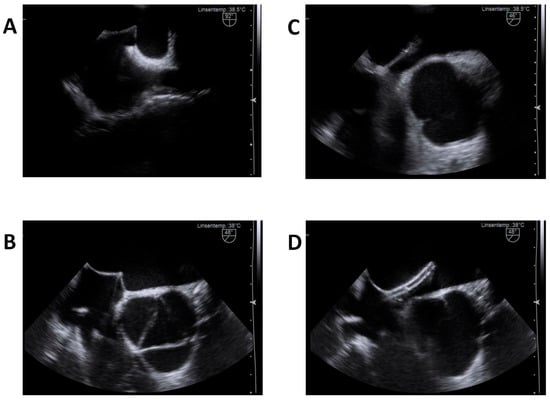

2.3. 2D-TEE Procedure